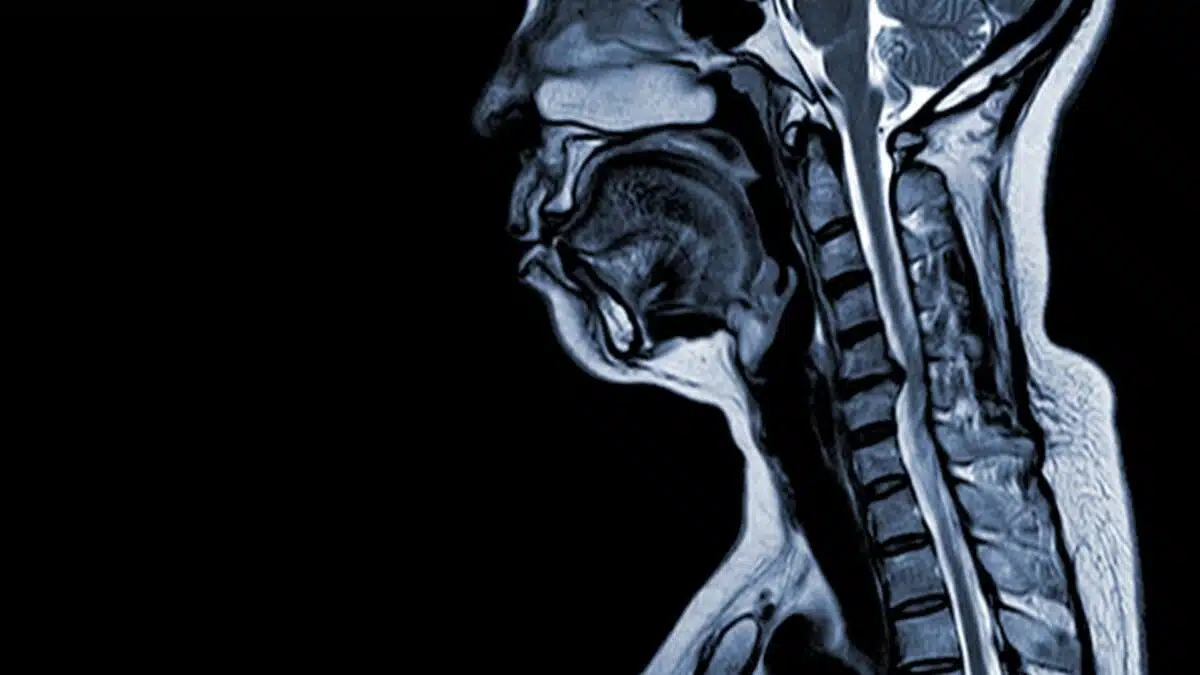

- Μαγνητική Τομογραφία (MRI): Παρέχει σαφή εικόνα της κατάστασης των σπονδύλων, των δίσκων και του νωτιαίου μυελού.